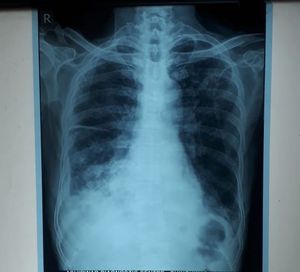

A male patient of age 80yrs. have complaints of cough since 1 month with expectorant and pain in chest while coughing. Also have fever from 10-15 days...

Right horizontal fissure is prominent (increased lung markings),both lower lobes infiltrates w/right blunted costophrenic angle.All this added to hx of age,cough,fever,chest pain, all point towards a lung infection(pneumonia ). I want lateral view CXR, Chest CT, sputum culture, thoracocentesis +cultures, CBC,PPD and start broad spectrum Abx while waiting for results. Also take a detailed history (social, personal, family,etc )

Its pleural effusion and to find out cause of fever we did regular check up in that typhoid reports are positive. Also patient was in dehydration so bp was 70/40mmhg. Wbc was 30000.

Blunting of costophrenic angle points to pleural effusion ( intercostal drainage) and treat with third gen cephalosporin for the infection (fever) after an infection screen